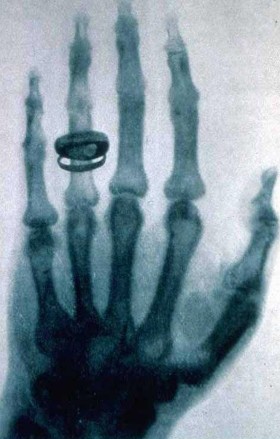

Zdjęcie rentgenowskie dłoni Rudolfa Kollikera wykonane przez Roentgena na posiedzeniu Physical Medical Society w Würzburgu 23 stycznia 1896.Wilhelm Conrad Roentgen/Wikipedia Zdjęcie rentgenowskie dłoni Rudolfa Kollikera wykonane przez Roentgena na posiedzeniu Physical Medical Society w Würzburgu 23 stycznia 1896.